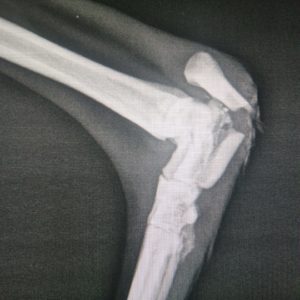

Santé : en cours, opérée pour sa fracture

Selma a été trouvée errante sur Linares avec une fracture. Nous avons été appelés d’urgence pour une galga trouvée avec la patte cassée… Elle est à la clinique et elle a été opérée (26/2/2020). Nous l’avons appelé Selma.